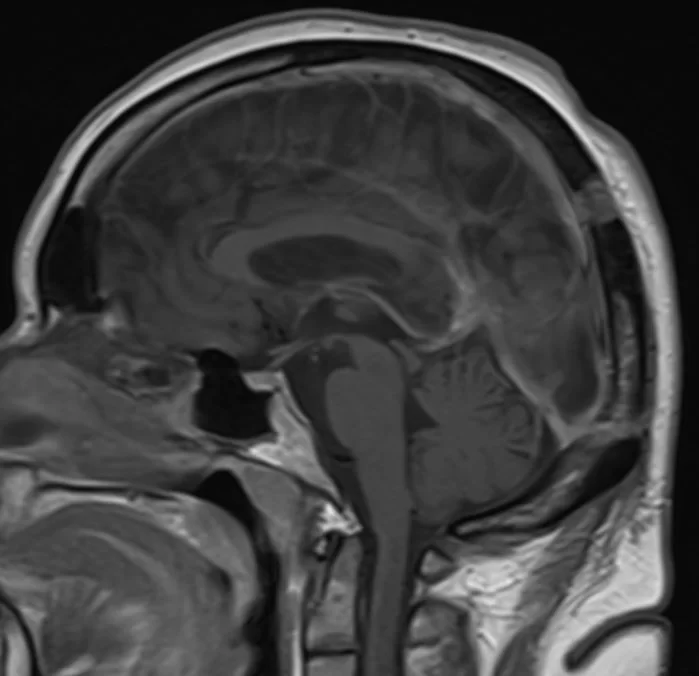

Ο απεικονιστικός έλεγχος με μαγνητική τομογραφία ανέδειξε ευμεγέθη όγκο στην περιοχή της επίφυσης (κωνάριο) με πίεση επί του μεσολοβίου, του τετραδύμου πετάλου και λοιπών εν’ τω βάθει δομών.